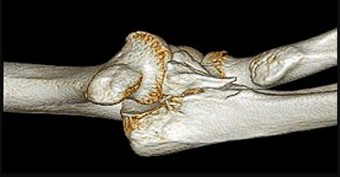

A 55-year-old man falls on his outstretched arm and sustains the injury shown in the 3-dimensional CT scans in Figures 1a and 1b.